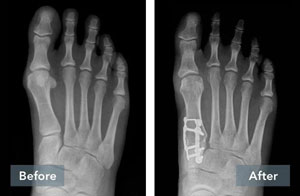

Lapiplasty® Before & After Results

The Positive Effect of Lapiplasty®

While traditional 2D osteotomy surgery merely cuts & shifts the bone to address the cosmetic bump, Lapiplasty® 3D Bunion Correction™ does more — it corrects the entire bone in 3D and secures the unstable foundation to get you back on your feet quickly in a walking boot. The Lapiplasty® Procedure has also shown low recurrence; 97% and 99% maintain 3D correction in 13 and 17 months respectively.